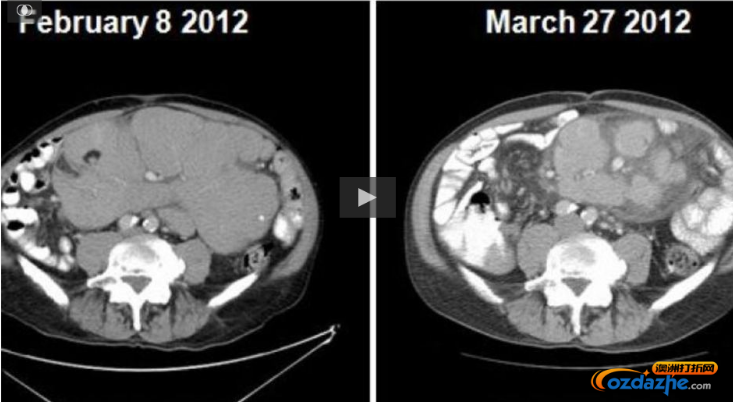

在此前美国的一项为期4年的针对慢性淋巴白血病的临床试验中,Venetoclax 在116名来自美国和墨尔本的患者身上显示出良好的效果。

实验结果表明,有80%的慢性淋巴性白血病(CLL)患者有明显疗效,癌细胞逐渐减少或消失,对慢性淋巴细胞白血病患者疗效良好!!!

另外有20%的患者,在参加试验后身体内的癌细胞竟然完全消失!!!被Venetoclax 完全治愈!!!